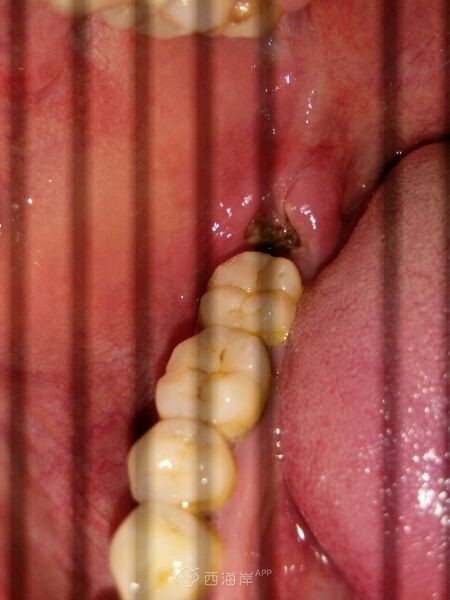

拔牙第三天,希望快点好

这样就能早点忘记让人恐惧的那一天